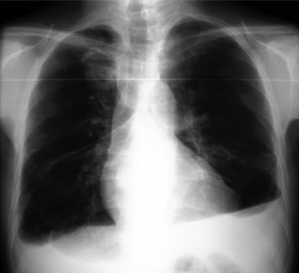

La infección por hongos filamentosos más frecuente fue la mucormicosis (82 casos), de los cuales 79 (96.3%) fueron de localización rinocerebral y tres de localización pulmonar (figura 2). En 85.3% (70 casos) los pacientes tenían cetoacidosis diabética, ocho presentaban inmunosupresión por diversas causas (enfermedad renal, tratamiento con esteroides, enfermedades autoinmunes, etc.) y en cuatro casos el único factor identificado fue la edad avanzada (> 65 años). De los 82 pacientes, 37 (45.12%) fallecieron, y de los sobrevivientes, 40 (88.9%) tuvieron secuelas permanentes debidas a cirugías o debridación quirúrgica extensa. El examen directo y el cultivo fueron positivos en 42 pacientes (51.2%); en los 40 pacientes restantes el diagnóstico se estableció por estudio histológico y/o examen directo. En los cultivos, el género identificado con mayor frecuencia fue Rhizopus sp. (26 casos, 31.7%), seguido por Mucor sp. (7 casos, 8.53%). Además, se obtuvo un aislado que correspondió a Syncephalastrum sp. y otro a Cunninghamella sp., en 7 casos se desarrollaron hongos filamentosos de micelio cenocítico sin estructuras morfológicas útiles para identificar el género.

Estudio radiológico de paciente con mucormicosis pulmonar que muestra una gran lesión en el lóbulo superior del pulmón derecho y múltiples imágenes radio-opacas diseminadas en ambos campos